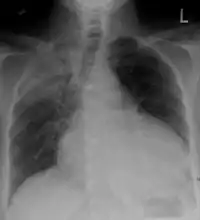

Chest x-ray: is non-specific and may not help identify a pericardial effusion but a very large, chronic effusion can present as "water-bottle sign" on an x-ray, which occurs when the cardiopericardial silhouette is enlarged and assumes the shape of a flask or water bottle.[2] Chest radiograph is also helpful in ruling out pneumothorax, pneumonia, and esophageal rupture.

A CT scan showing a pericardial effusion

Pericardial effusion due to malignancy. Note bulbous heart and primary lung cancer in right upper lobe.